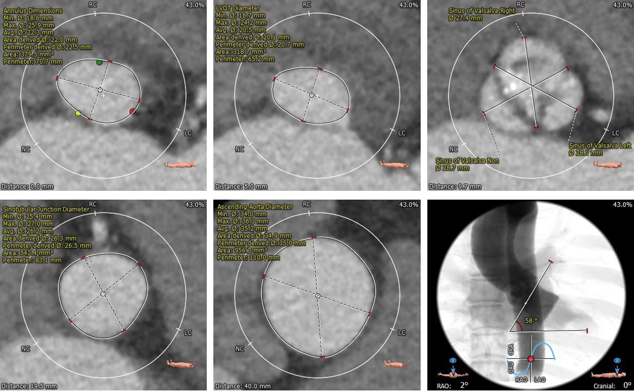

术前CT评估:

主动脉根部:

三叶式主动脉瓣,瓣环直径约22.5mm,LVOT呈收口型STJ、升主动脉内径可,非横位心,瓦氏窦较小。

冠脉测量:

左、右冠脉开口高度尚可,瓣叶长于冠脉开口下缘

钙化测量:

轻度钙化,左、无窦瓣叶纤维融合

入路测量:

股动脉入路可

风险评估:

• 三叶式主动脉瓣,瓣叶增厚,轻度钙化,收口型LVOT,锚定难度适中,存在瓣膜移位风险